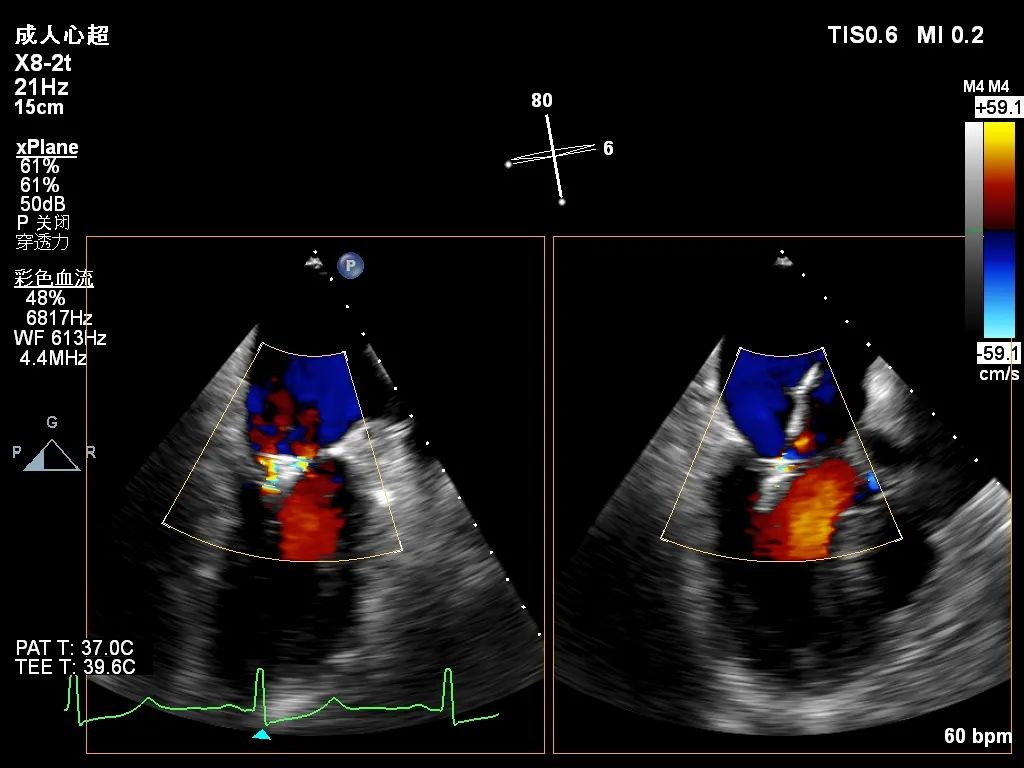

术前超声心动图

术后超声心动图

心脏超声检查提示:二尖瓣后叶(P2)脱垂,并存在腱索断裂,重度二尖瓣反流。

患者在麻醉科团队保驾护航下,器械经股静脉穿刺房间隔,通过输送系统送入左心房,到达二尖瓣瓣膜反流处,在经食道超声心动图及DSA引导下,术者通过反复评估二尖瓣膜脱垂范围、抓捕位置、反流程度之后,进行精准夹合,成功植入DragonFly瓣膜夹1枚。术后超声即刻患者反流降低至轻度,二尖瓣跨瓣平均压差未超过4mmHg,左房压下降,肺静脉逆流减轻,血流动力学改善明显,手术取得圆满成功。